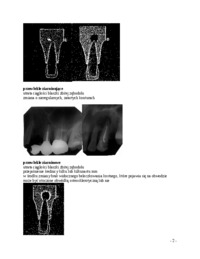

Anatomia radiologiczna 1. Anatomia radiologiczna zęba oraz przyzębia. 2. Anatomia radiologiczna szczęki. 3. Anatomia radiologiczna żuchwy. 4. Struktury anatomiczne widoczne na zdjęciu pantomograficznym. 5. Anatomia radiologiczna czaszki. Anatomia radiologiczna zęba i przyzębia Zróżnicowanie p...